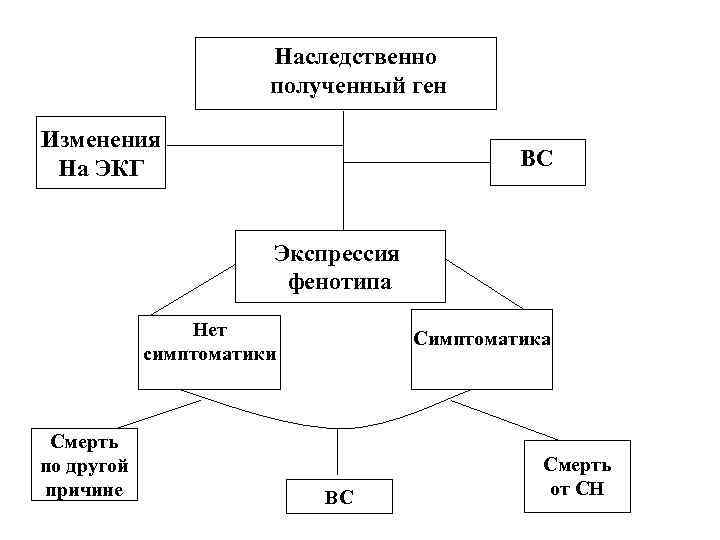

Наследственно полученный ген Изменения На ЭКГ ВС Экспрессия фенотипа Нет симптоматики Смерть по другой причине Симптоматика ВС Смерть от СН

Наследственно полученный ген Изменения На ЭКГ ВС Экспрессия фенотипа Нет симптоматики Смерть по другой причине Симптоматика ВС Смерть от СН